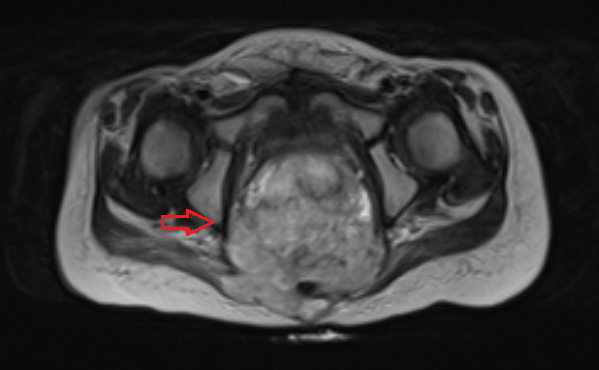

Яичники

Овариальные (расположенные в яичниках, яичниковые) опухоли наиболее часто проявляются болью в животе. При осмотре пальпируется опухоль в малом тазу, часто - в брюшной полости. Также за счет асцита (скопления в брюшной полости жидкости) увеличен живот. Нередко у девочек с таким диагнозом бывает лихорадка.

Рисунок 3. - тератома яичника а -УЗИ, б — МРТ.

- УЗИ. «Ультразвук» нужен для того, чтобы выявить первичный очаг как гонадной (в половых органах), так и внегонадной герминогенной опухоли. Его также проводят в ходе терапии, чтобы оценить ее эффективность.

- КТ (расшифровка: компьютерная томография), МРТ (расшифровка: магнитно-резонансная томография), ПЭТ-КТ (расшифровка: позитронно-эмиссионная томография, совмещенная с КТ). Эти обследования необходимы, чтобы рассмотреть структуры организма послойно и визуализировать опухоль. Они показывают, как сильно распространен патологический опухолевый процесс на находящиеся рядом ткани и органы, есть ли поражение костей. КТ - это самый чувствительный метод для обнаружения метастазов в легких. Проведение МРТ и КТ головного мозга необходимо, чтобы обнаружить и визуализировать герминогенные новообразования эпифиза.